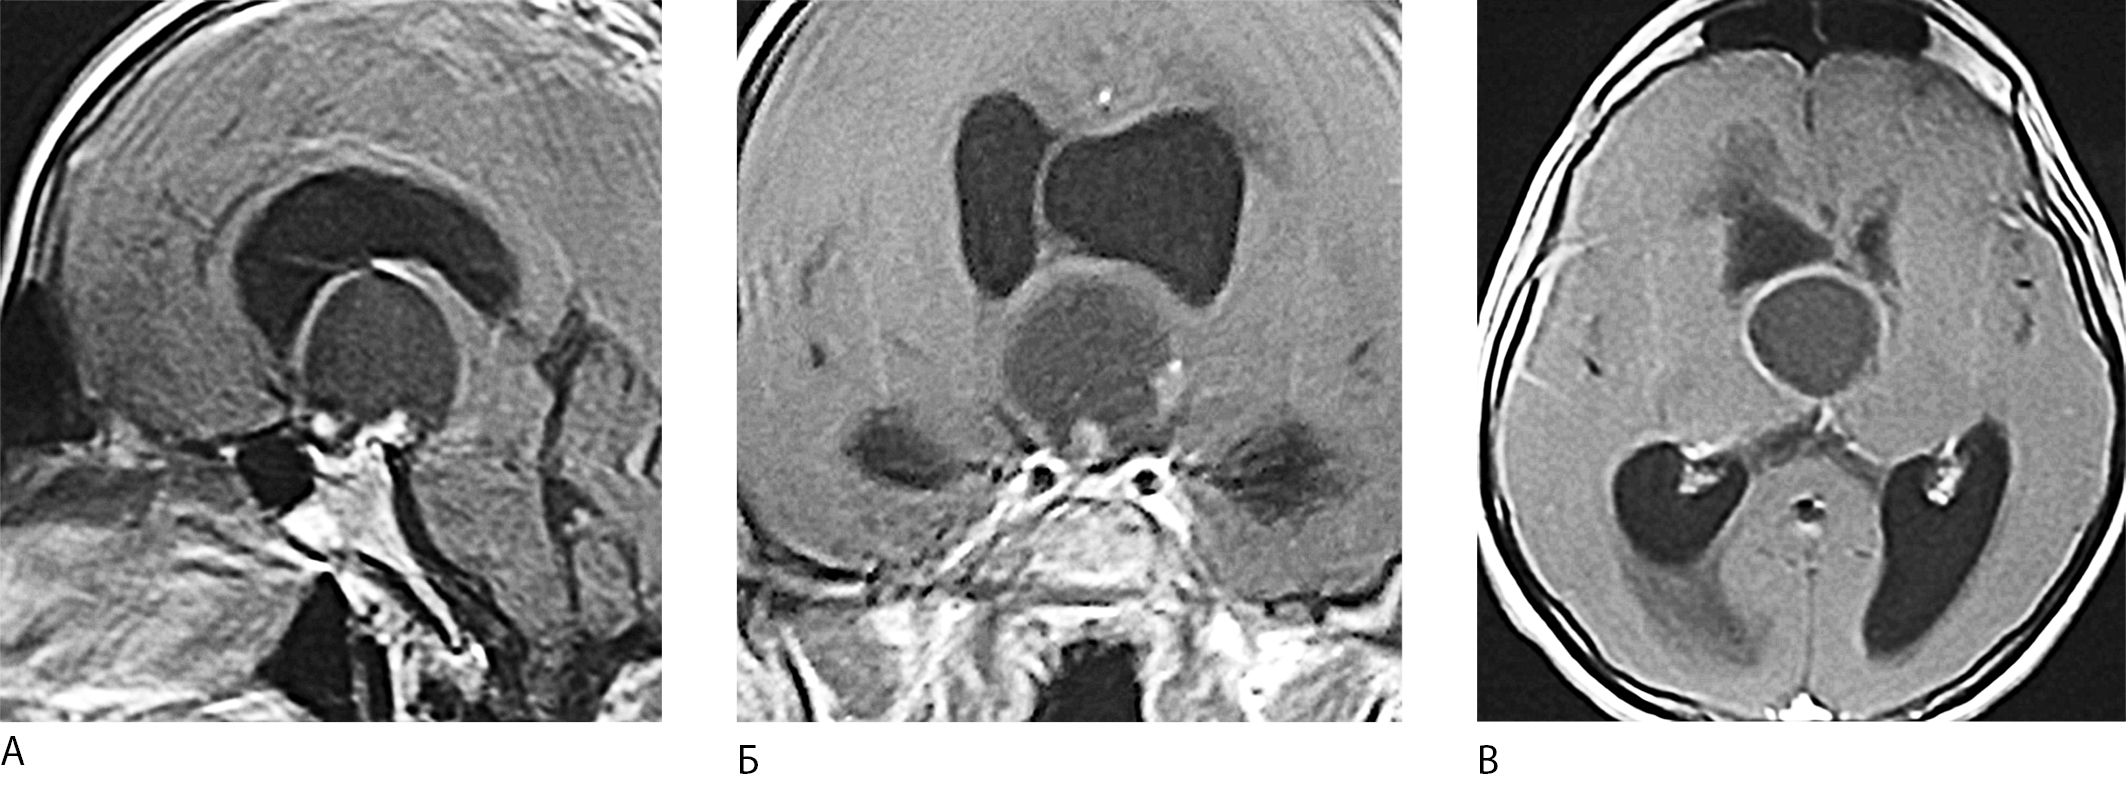

При магнитно-резонансной томографии (МРТ) головного мозга выявлялось кистозное образование, расположенное в супраселлярной области и в проекции Ш желудочка, поддавливающее отверстие Монро, что вызывало расширение боковых желудочков с умеренными явлениями перивентрикулярного отека (рис. 1А, Б, В). При ЭЭГ исследовании – эпилептической активности не выявлено. Ультразвуковая допплерография (УЗДГ) сосудов головного мозга и шеи – без особенностей.

Рис. 1. МРТ пациента Р-ва 39 лет с кистозной краниофарингиомой до операции (плоскости: А - сагиттальная; Б - фронтальная; В - аксиальная).

1. Рис. 1. МРТ пациента Р-ва 39 лет с кистозной краниофарингиомой до операции (плоскости: А - сагиттальная; Б - фронтальная; В - аксиальная). | |